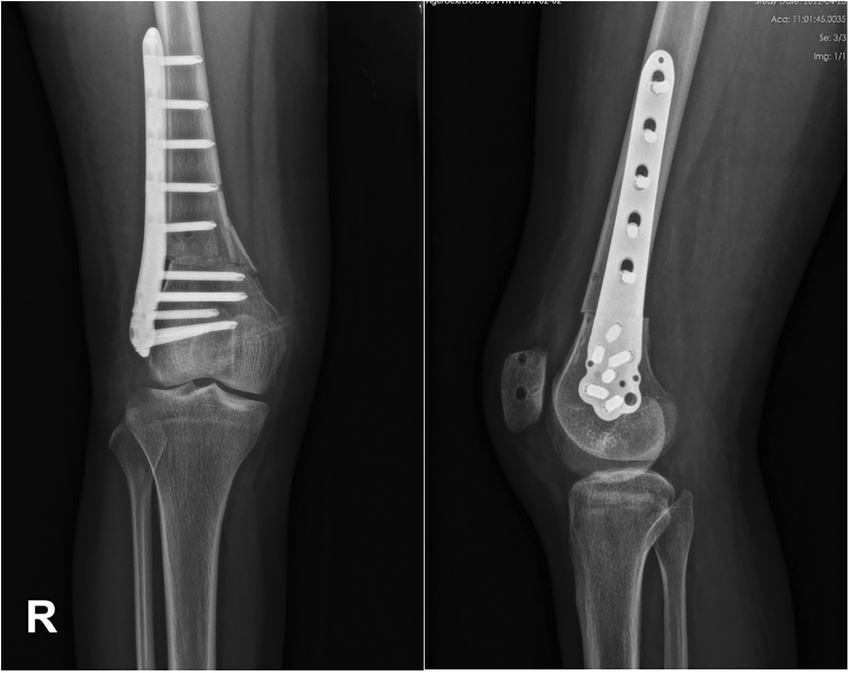

In some cases, MPFL reconstruction may be combined with other procedures, such as a tibial tubercle osteotomy (TTO), to better correct the alignment of the kneecap and reduce the risk of future dislocations.

- Standard X-rays can show if the kneecap is abnormally positioned or if there is damage to the bone surfaces after a dislocation.

- Special views such as a skyline or Merchant view may be used to see how the patella sits in the groove of the femur.

- Sometimes used for detailed measurements of bone alignment, such as the TT–TG (tibial tubercle to trochlear groove) distance.

- May help guide surgical planning if multiple structural issues are present.

Concurrent procedures

- Tibial Tubercle Osteotomy (TTO): to realign the patella.